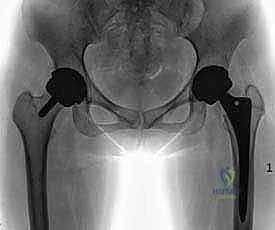

على عكس عملية "الاستبدال الكامل لمفصل الورك" (Total Hip Replacement - THR) التي يتم فيها قطع وإزالة رأس عظمة الفخذ بالكامل مع جزء من عنق العظمة لزرع جذع معدني طويل داخل التجويف العظمي، فإن تقنية استبدال السطح تقوم فقط بإزالة الغضروف المتآكل والطبقة السطحية التالفة من العظم. بعد ذلك، يتم "تغليف" أو "تلبيس" رأس عظمة الفخذ الطبيعي بغطاء معدني أملس (يشبه التاج الذي يوضع على السن التالف)، ويتم وضع قبة معدنية أخرى داخل تجويف الحُق (Socket) في الحوض.

4. تركيب الغطاء المعدني (Femoral Component)

يتم تثبيت التاج أو الغطاء المعدني الأملس فوق رأس عظمة الفخذ المنحوت، وغالباً ما يتم تثبيته باستخدام مادة أسمنتية طبية خاصة لضمان ثباته المطلق.

5. تحضير وتلبيس تجويف الحُق (Acetabular Component)

يتم تنظيف تجويف الحوض (الحُق) من الغضاريف المتآكلة باستخدام مبشرة طبية، ثم يزرع وعاء معدني (Cup) داخل التجويف. هذا الوعاء يثبت عادة عن طريق الضغط (Press-fit) حيث ينمو العظم الطبيعي لاحقاً حوله ليثبته بقوة.

6. إرجاع المفصل والإغلاق

يتم إعادة رأس الفخذ المغلف بالمعدن إلى داخل الوعاء المعدني في الحوض. يقوم د. هطيف باختبار نطاق الحركة والتأكد من استقرار المفصل وعدم قابليته للخلع، ثم يتم إغلاق الشق الجراحي تجميلياً.